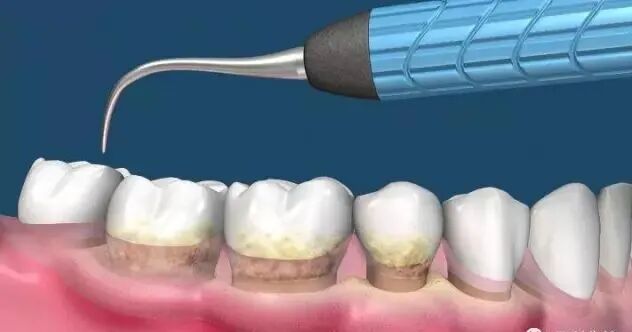

洗牙!医生口中的:全口龈上、下洁治术。当当当当!闪亮登场!

(洁牙中)

刷牙用牙线可以去除牙齿表面及牙间隙的污垢,可是,即使是每天定时正确刷牙和用牙线,仍然会有30%左右软垢躲藏在隐蔽角落无法清理干净。久而久之,含有大量细菌的软垢和唾液中矿物质结合逐渐变硬成为牙结石。细菌是导致牙龈炎的、牙周病的罪魁祸首,虽然牙结石本身是已经坏死的细菌并不会引起牙龈炎。

事实上,只有专业洗牙才会彻底清除普通刷牙无法去除的牙结石,细菌毒素及牙齿表面沉积的色素。同时,定期洗牙也会尽早发现不易察觉的牙病,及时消除隐患。